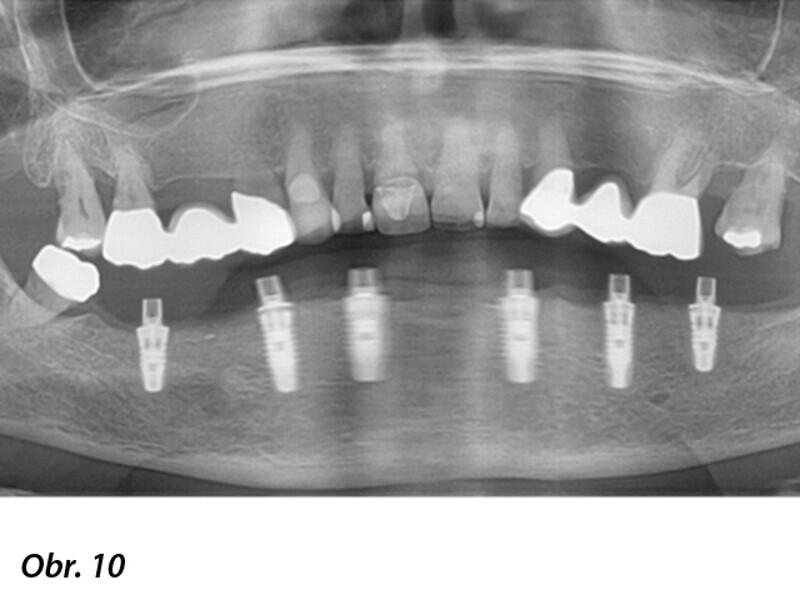

Počítačem asistované, šablonou se řídící okamžité zavedení a zatížení implantátu v dolní čelisti